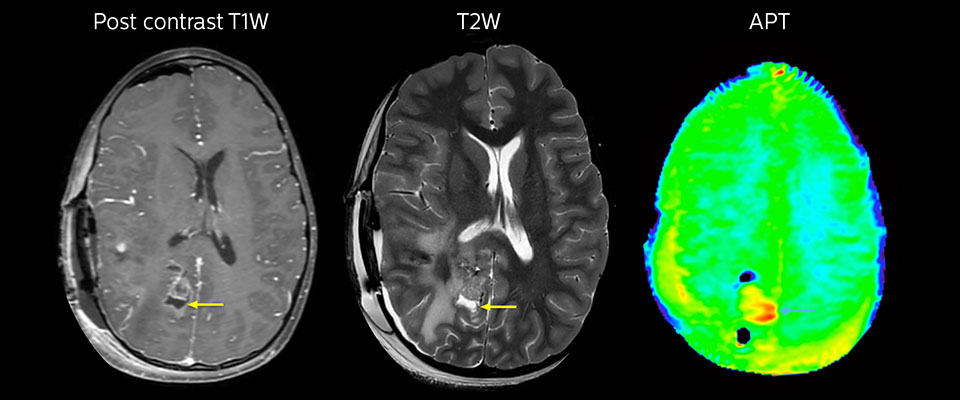

MRI with APT post resection

Immediately post resection MRI was again performed. T2-weighted and postcontrast T1-weighted images are quite inconclusive for distinguishing residual tumor tissue from postoperative tissue changes. On the APT image some high signal is still seen, which would suggest residual tumor tissue.

Follow-up over time

In later follow-up scans the post-contrast T1-weighted images suggest recurrent tumor growth. So, it would be interesting to study the predictive value of APT in a large patient group.